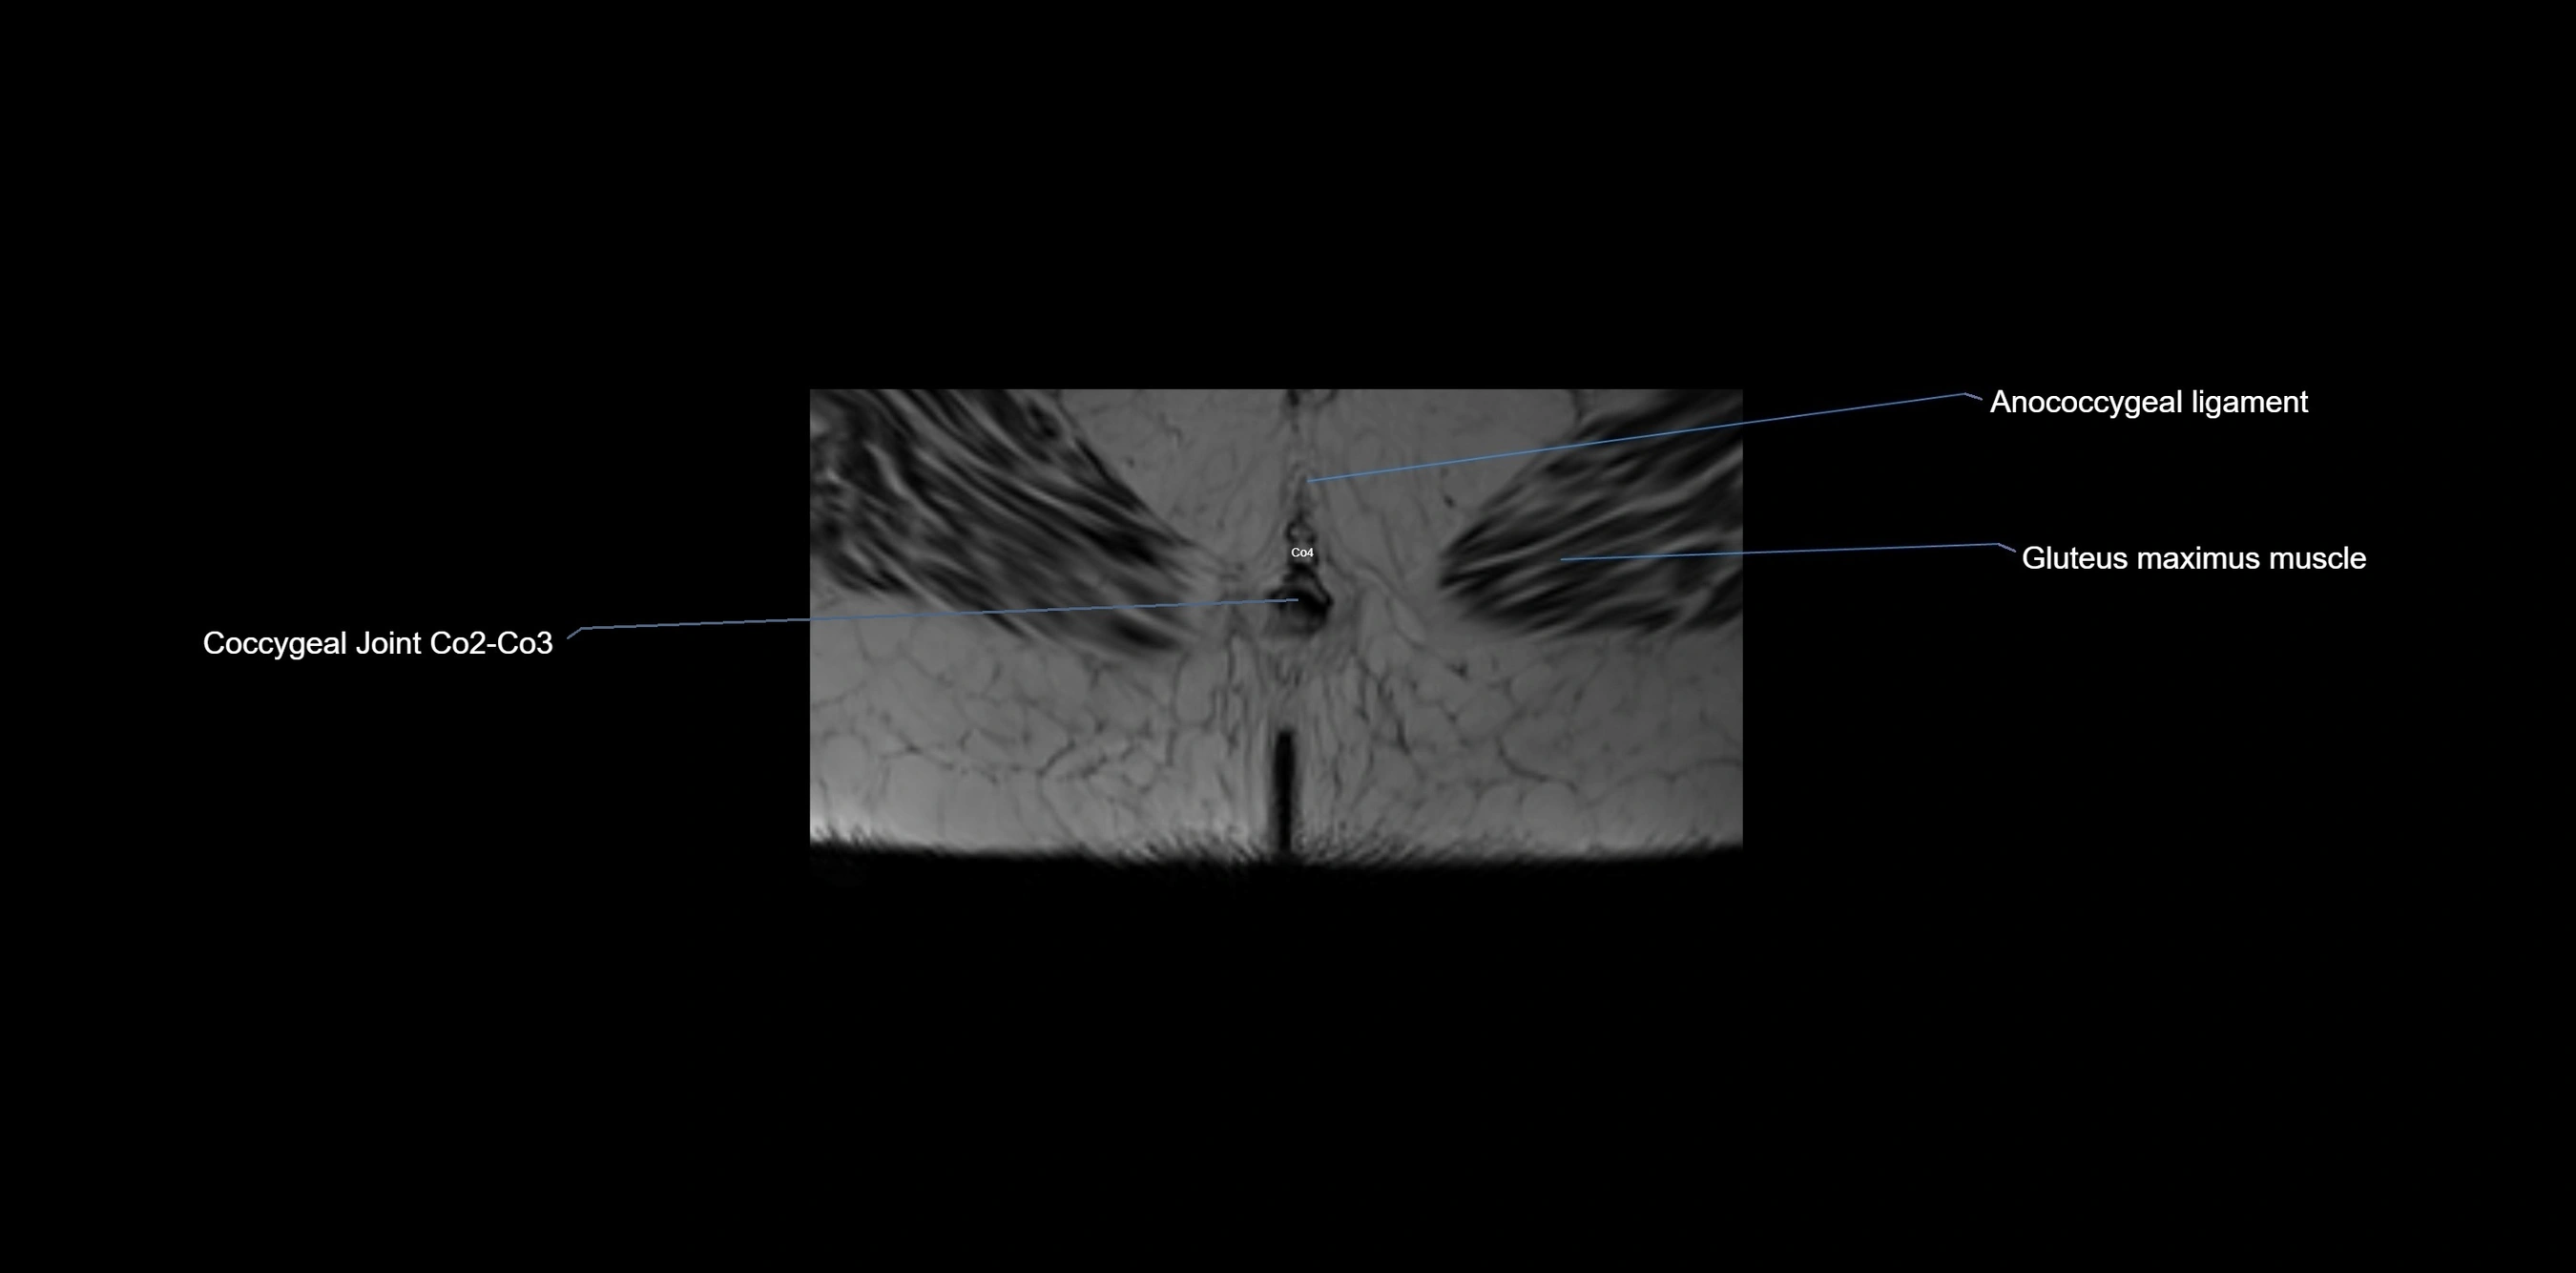

MRI Appearance

T1-weighted images:

• Cortical bone appears very low signal (dark); marrow shows intermediate signal

• Iliac fossa fat is bright against low-signal cortex

T2-weighted images:

• Cortical bone remains dark

• Marrow signal varies depending on fat content; edema or tumor shows hyperintensity

STIR:

• Suppresses fat, making bone marrow edema, fractures, or infiltrative lesions appear bright

• Excellent for trauma, sacroiliitis, and metastatic evaluation

T1 Fat-Saturated (Pre-contrast):

• Marrow: intermediate signal, fat suppressed

• Useful for detecting subtle marrow abnormalities adjacent to iliac cortex

T1 Fat-Saturated Post-Contrast (Gadolinium):

• Enhances vascularized structures, marrow pathology, tumors, and inflammatory changes

• Highlights soft tissue or bone invasion in pelvic neoplasms

MRI Non-Contrast 3D Imaging:

• Provides 3D morphology of iliac wing, crest, and articulations

• Used in preoperative planning for pelvic surgery and trauma reconstruction